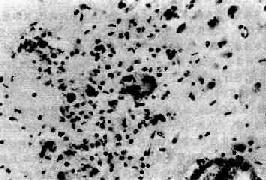

脑和脊髓充血明显,病变一般在神经根节、脑干下端、下丘脑等部位最为显著。镜下,可见弥漫性急性脑脊髓炎变化,有不同程度的神经元损害,从变性到坏死及神经细胞被吞噬;血管周围有淋巴细胞、浆细胞浸润,形成血管套。神经细胞内出现特征性的Negri小体具有病理诊断意义。该小体是神经细胞浆内的包含体,呈圆形或椭圆形,边界清楚,体积大,呈嗜酸性着色,多见于海马锥体细胞、小脑Purkinje细胞和大脑锥体细胞。每一神经细胞胞浆中小体的数目从一个到数个不等(图16-17)。炎症病变严重的部位,Negri小体数目往往不多。

图16-17 狂犬病

神经细胞胞浆中Negri小体

Negri小体含有病毒核壳体(核酸与蛋白质外膜组成),可用免疫组化加以显示,但电镜下看不到病毒颗粒。由于中枢神经系统中的病毒可沿周围神经离心性播散而侵入其他组织,故用免疫组化染色法可从皮肤活检或角膜细胞中检出Negri小体。当患者疑为疯狗咬伤时,应保留该狗数天,处死后检查其脑部,寻找Negri小体以帮助确诊。

4.亚急性脑炎 亚急性脑炎是AIDS的主要中枢神经系统病变,约有30%的AIDS尸检病例可检出此病变。病变主要累及大脑和小脑的白质,以及深部皮质。在程度不等的脱髓鞘病灶中可见巨噬细胞浸润,多核巨细胞形成(图16-18),在某些多核巨细胞胞浆中可检出HIV病毒颗粒或病毒蛋白(如P24)。淋巴细胞浸润程度较轻,主要在血管周围,且多为CD8+T细胞。此外还可有反应性星形胶质细胞增生,神经元也有一定程度的缺失。临床上可出现进行性精神和行为异常,精神淡漠,共济失调,震颤,终致出现AIDS痴呆综合征。然而痴呆的确切发病机制尚待阐明。

图16-18 AIDS亚急性脑炎

示病灶内形成的不典型多核巨细胞